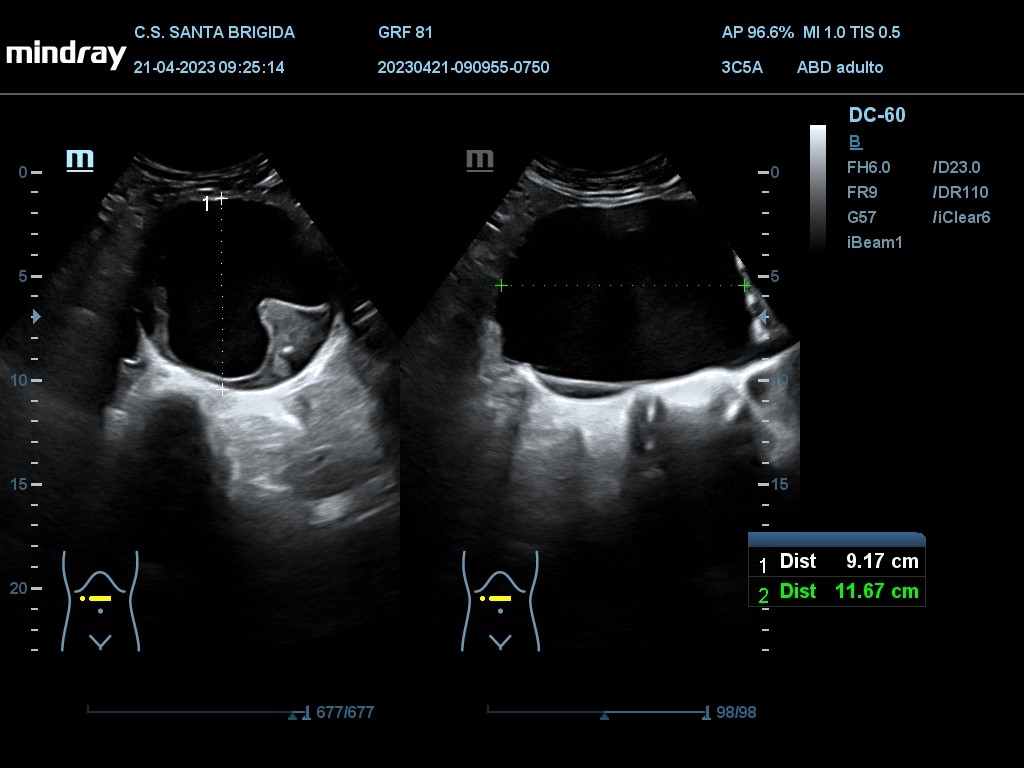

En ecografía clínica se aprecia dilatación de aorta abdominal de extensión máxima de 13,27 cm con origen proximal a la bifuración de las arterias renales y con un diámetro máximo de 9,91 cm. Además asocia imagen hiperecogénica respecto a la luz del vaso en la práctica totalidad de su recorrido en probable relación con trombo intramural semilunar de 3,7 cm.